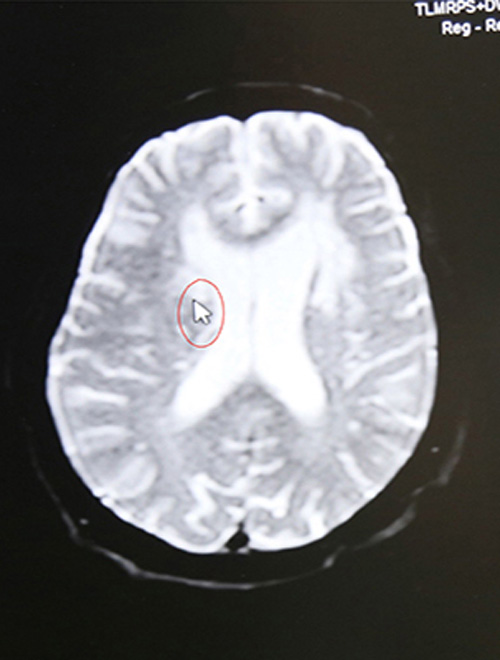

顱腦MRI示:右側(cè)基底節(jié)區(qū)腦梗塞

16:44 影像科3分鐘出報(bào)告,CT報(bào)告顯示:排除腦出血。為進(jìn)一步查看腦血管情況,又迅速完成了顱腦血管磁共振檢查,結(jié)果顯示:腦梗塞。

(結(jié)合影像學(xué)檢查,了解到老人有腦梗發(fā)病史,李振并主任判斷患者系急性腦梗,發(fā)病時(shí)間為15:30,還處于靜脈溶栓治療3小時(shí)的時(shí)間窗內(nèi),有溶栓治療指征,可溶栓治療,積極治療血管有再通希望。)